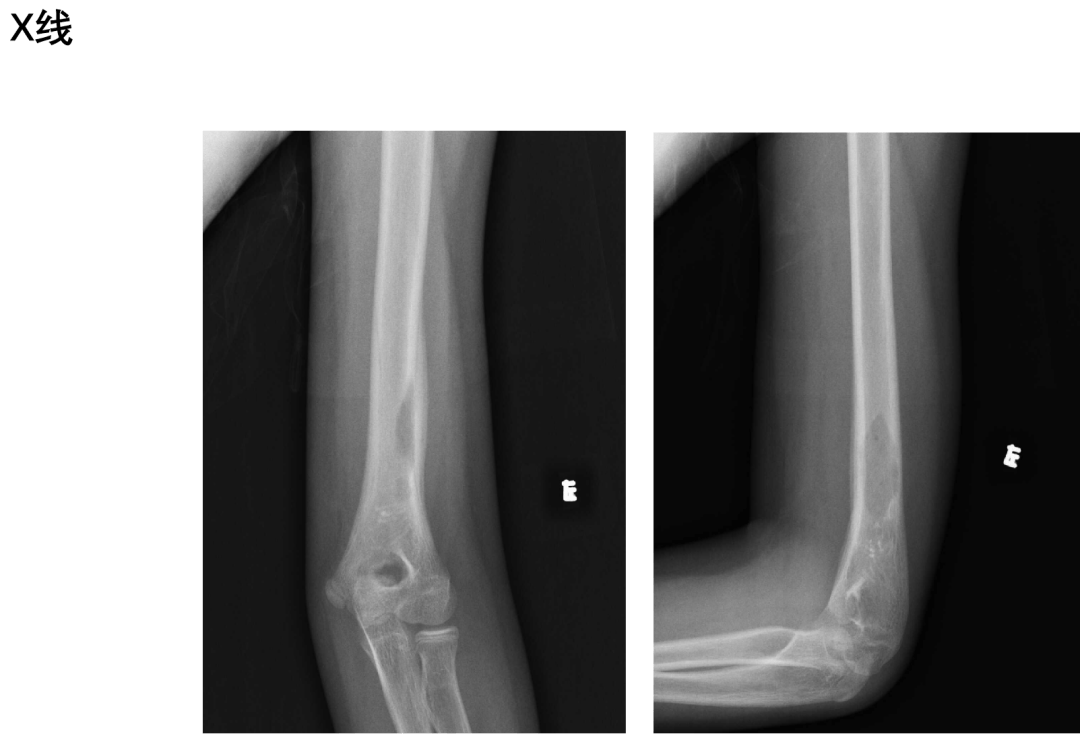

病例(女性,10岁)

主诉:左上臂疼痛2月余。

影像表现:

1.定位:左肱骨下段,单发,较局限

2.骨质破坏方式:溶骨性骨质破坏,穿透骨皮质

3.病灶密度;相对均匀,无肿瘤骨、死骨形成,无钙化及脂肪成分

4.病灶边缘:清晰,无硬化边

5.骨膜反应:有

6.信号特点:T1WI呈等低信号,T2WI高信号为主,伴临近骨质及周围软组织水肿,增强扫描不均匀强化,无增粗供血动脉及异常引流静脉